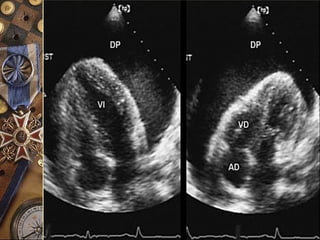

TAPONAMIENTO CARDÍACO  Enausencia de derrame imposible  Bamboleo cardíaco  Colapso de VD ( Especificidad = 100%)  Colapso de AD ( Sensibilidad = 100%) ECOCARDIOGRAMAECOCARDIOGRAMA

ECOCARDIOGRAFÍA  Es unexcelente método para el diagnóstico  Confirma la presencia de derrame pericárdico y brinda datos sugestivos de taponamiento cardiaco  La ausencia de pruebas ecocardiográficas de derrame pericárdico excluye virtualmente el dx de taponamiento

• 49.

ECOCARDIOGRAFÍA

 Es un excelente método para el

diagnóstico

 Confirma la presencia de derrame

pericárdico y brinda datos sugestivos de

taponamiento cardiaco

 La ausencia de pruebas ecocardiográficas

de derrame pericárdico excluye

virtualmente el dx de taponamiento

 El taponamiento es un continuum.

 Más que su presencia o ausencia lo que el

clínico debe valorar es su gravedad.